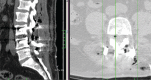

Trauma is a common cause of pneumocephalus, or air in the cranial cavity, and of pneumorrhachis, or the presence of intraspinal air. After spinal surgery, occurrence of pneumocephalus, especially with pneumorrhachis, is extremely rare. We report the case of a patient who developed pneumocephalus and pneumorrhachis after lumbar disc surgery and pedicle screw fixation. There was no cerebrospinal fluid leakage during surgery. On postoperative day 1, the patient complained of headache, nausea, and dizziness. Brain and lumbar computed tomography scans revealed pneumocephalus and pneumorrhachis. With conservative treatment, the patient's complaints resolved within 10 days.